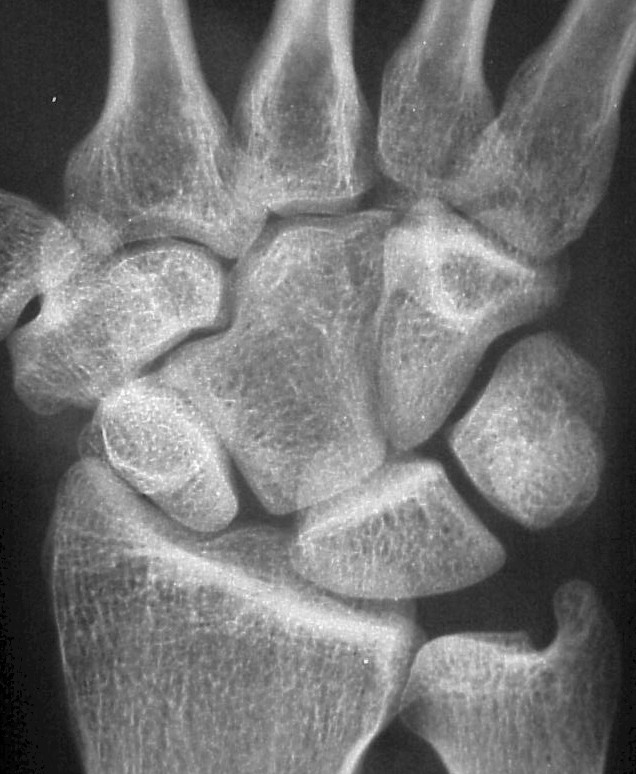

Plain films demonstrate an unusual capitate contour, articulating with the proximal trapezoid. There is a wide scapholunate interval.

The scapholunate angle is abnormal, about 80 degrees.